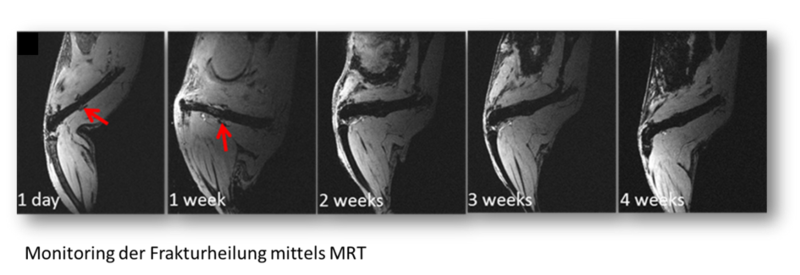

Schmitz N, Timmen M, Kostka K, Hoerr V, Schwarz C, Faber C, Hansen C, Matthys R, Raschke MJ, Stange R (2020) A novel MRI compatible mouse fracture model to characterize and monitor bone regeneration and tissue composition. Sci. Rep. 2020 Oct. 1;10(1):16238. doi: 10.1038/s41598-020-73301-y.